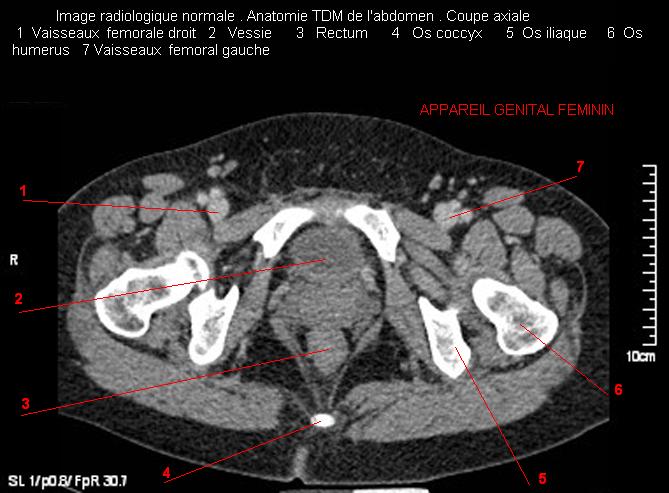

Image radiologique TDM normale de l'abdomen et tube digestif en coupe axiale ( CT scanner )  :

Coupe axiale     Coupe frontale      Coupe  sagitale